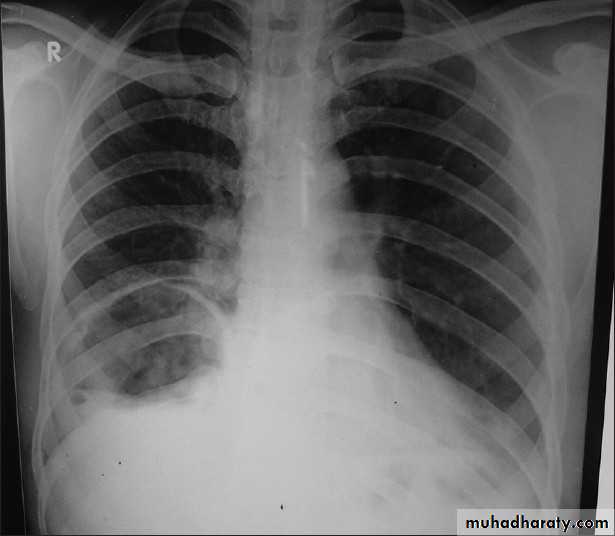

X-ray hemothorax

X-ray pneumohemothorax

X-ray Empyema